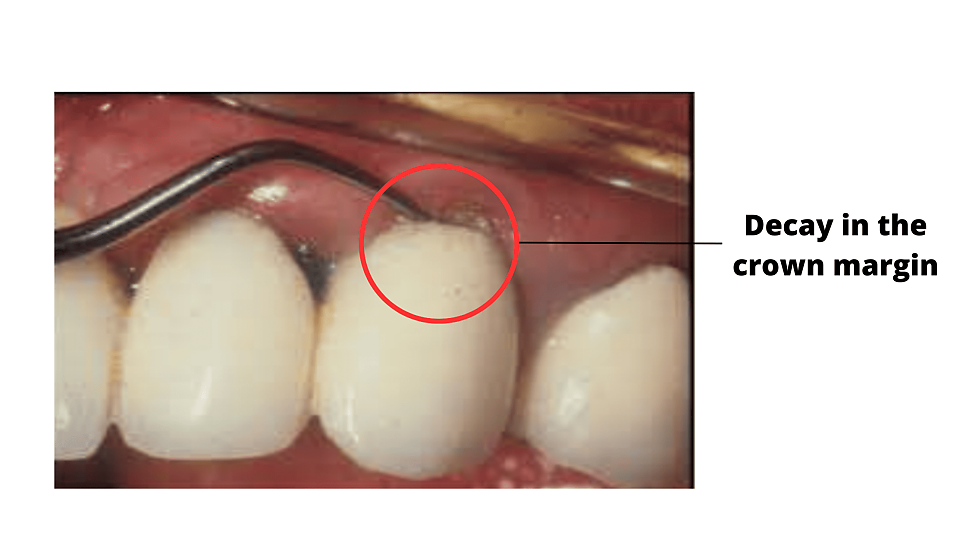

위 그림처럼 크라운의 마진, 즉 가장자리 부분에 관리가 잘 안되게 되면 치아가 썩어 문제가 발생할 수 있습니다. 크라운의 가장 흔한 문제점 중 하나이죠. (출처: https://www.tooth-life.com/cavity-under-crown.php)